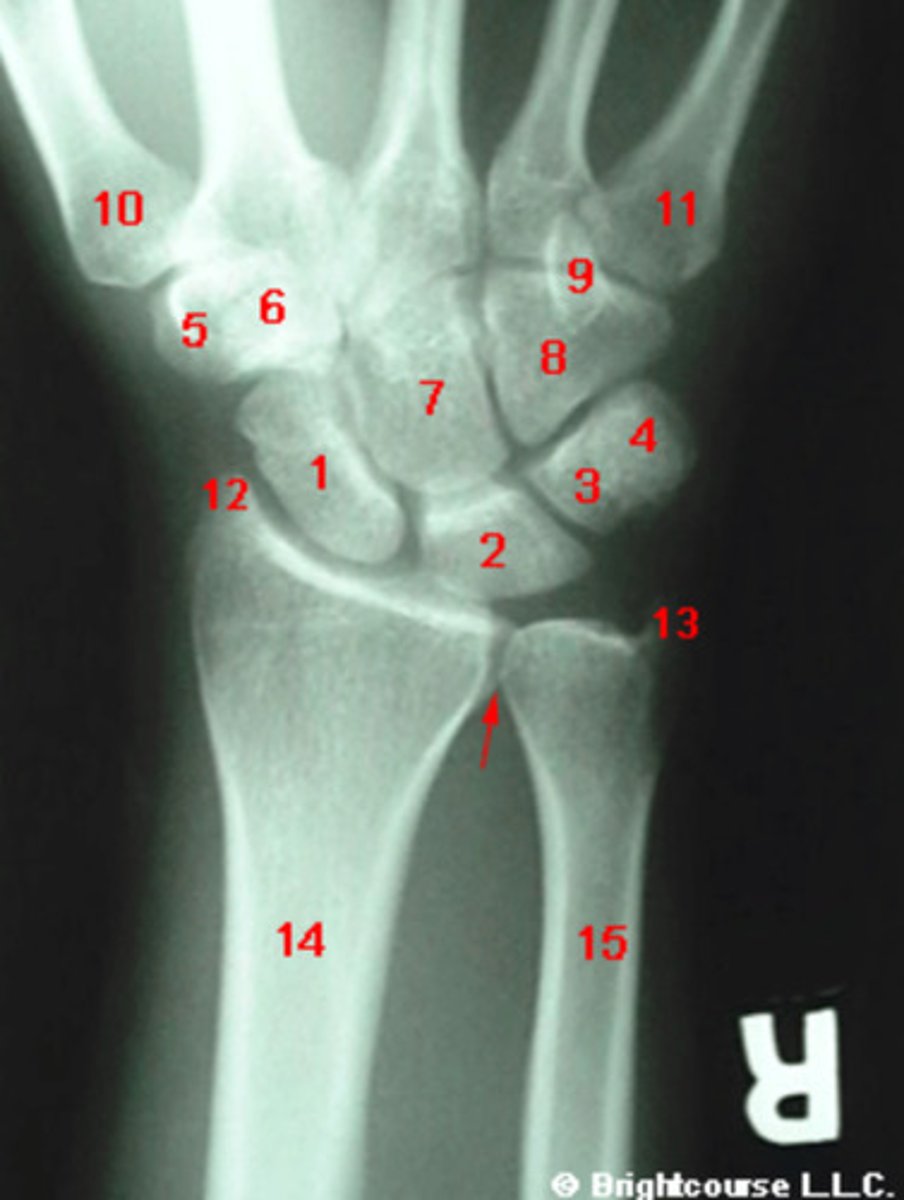

PA, internal oblique, and lateral

What are the standard plain film radiographic projections for the wrist?

What structure is indicated by number 7?

What structure is indicated by number 1?

What structure is indicated by number 2?

What structure is indicated by number 3?

What structure is indicated by number 4?

What structure is indicated by number 5?

What structure is indicated by number 6?

What structure is indicated by number 8?

What structure is indicated by number 13?

What structure is indicated by number 12?

What structure is indicated by number 9?

What structure is indicated by number 10?

Radius angle

What angle is being assessed in this image?

Radioulnar angle